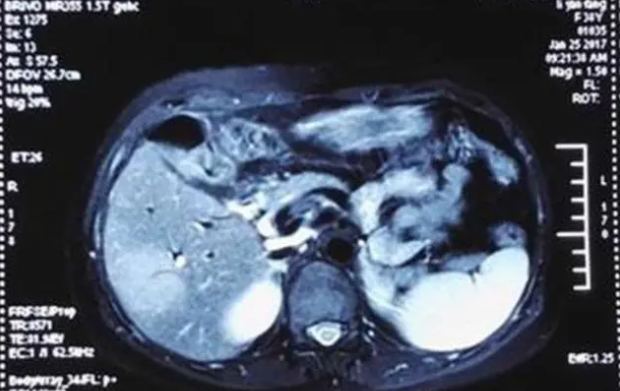

女子3次试管婴儿终于怀上却查出癌症,面对巨大选择难题该怎么办?

33岁的阿珂经历三次试管之后,终于成功孕育了小生命,却被...